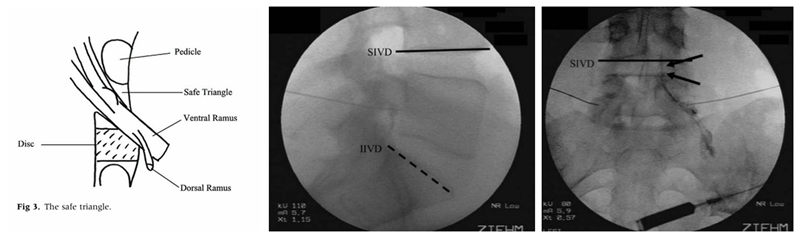

Sub-pedicular(SP)入路注射的提出

既然我们只需要把药物注射至神经根的周围而没必要注射至神经根鞘膜内,那么有没有一个更安全固定的穿刺点可以选择呢?答案是肯定的。Bogduk等提出了一种新的注射方法,该方法是将穿刺靶点设定在神经根的肩上,椎弓根的下方,Bogduk将这种方法称之为Sub-pedicular(SP)入路。穿刺的靶点称为安全三角(safe triangle):即椎弓根的下缘水平线,椎间隙外侧的垂直线和出椎间孔神经根的外缘线。该穿刺靶点有明确的骨性结构作为标志,可在影像引导下进行,同时将穿刺针尖远离了神经根。因此,提出了MRI椎间盘退变分型的Pfirrmann教授也发文力挺该方法,他认为在影像引导下采用这种方法进行脊柱注射术,是安全和精确的(safe and accurate)。SP入路很快便得到了广泛的认可和推广,至今仍有部分疼痛科医师使用。

图5

对各种注射方法的研究在当时激起了人们很大的兴趣,也随之出现了各种不同的称呼:神经根浸润术(nerve root Infiltration)、选择性神经根阻滞术(selective nerve root blocks)、选择性硬膜外注射术(selective epidural injections)、经椎间孔神经根注射术(Transforaminal nerve root injection)等。2003年,ISS(International Spinal Intervention Society, 国际脊柱介入学会)根据SP入路的特点,建议使用 Transforaminal injection一词。